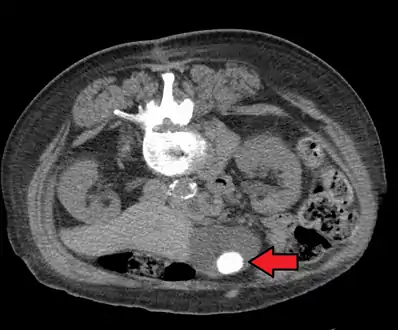

Diagnosis

Diagnosis is typically confirmed by abdominal ultrasound. Other imaging techniques used are ERCP and MRCP. Gallstone complications may be detected on blood tests.[2]

On abdominal ultrasound, sinking gallstones usually have posterior acoustic shadowing. In floating gallstones, reverberation echoes (or comet-tail artifact) is seen instead in a clinical condition called adenomyomatosis. Another sign is wall-echo-shadow (WES) triad (or double-arc shadow) which is also characteristic of gallstones.[38]